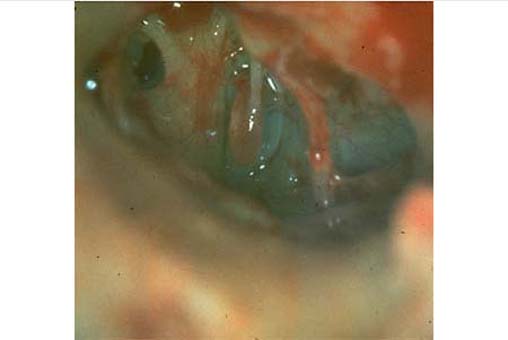

"kleine Missbildungen": Fehlen des langen Ambossfortsatzes